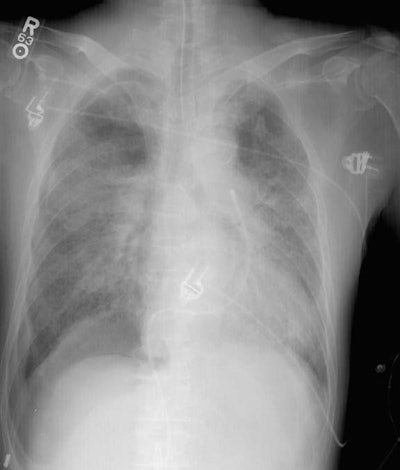

Repeat exam:

The repeat exam demonstrates the "deep sulcus" on the right, as well as a pleural line in the right upper lung indicating that the pneumothorax had enlarged in the interval from when the initial film was performed.